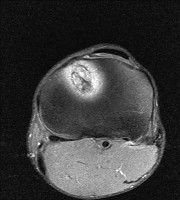

무릎 mri 간단히 봐주실 수 있으시나요 ㅠㅠ

안녕하세요 8년전 십자인대 수술하고 최근 무리한 운동에 무릎 불편감이 생겨서

mri 찍었습니다.

진단결과는 첫 찍은 병원에서 활액막염 이라는 진단을 받았습니다. 혹시 봐주실 수 있으실까요?

올라온 MRI가 단편적이라서 정확한 진단에 어려움이 있지만 십자인대에는 큰 이상이 있지는 않은것 같으며, 무릎관절내 물이 있는 것으로 보아 활액막염의 진단이 맞을 것 같습니다.

하지만 단편적인 영상이기 때문에 촬영병원에서 정확한 판독지 등을 받으시는 것이 좋겠습니다.